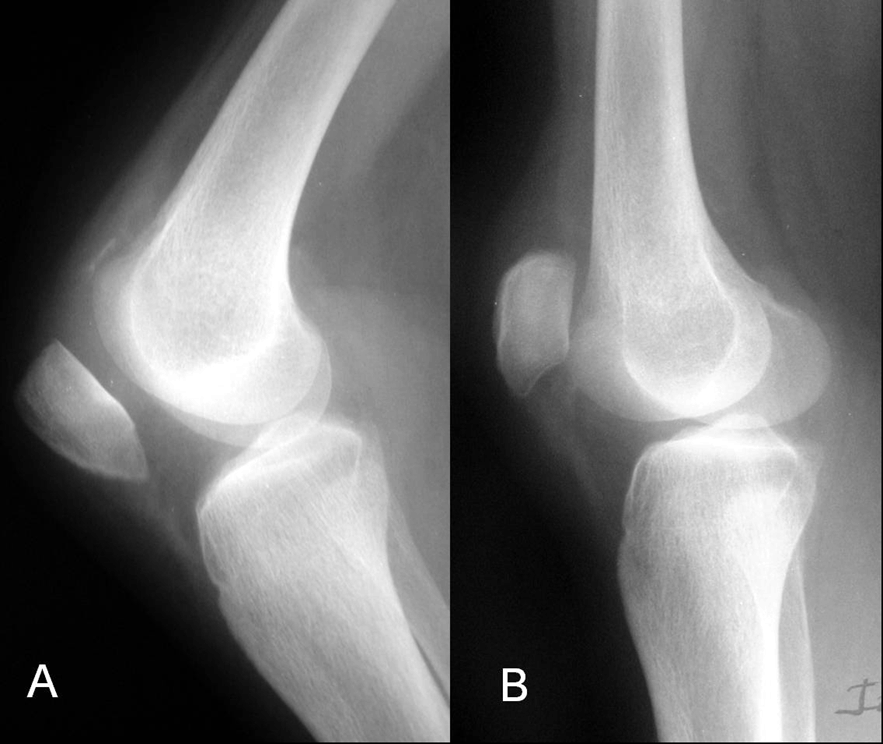

A 31-year-old female suffered sudden pain and loss of extension of both the knees after trying to get up from a sofa. No previous injuries of the knees or intensive sports activities were recorded. Her personal history consisted of chronic renal failure due to renal tubular acidosis diagnosed at the age of eight years and since then she was receiving maintenance hemodialysis until 1984, when a renal transplantation was performed. The transplantation failed six years later and a transplantectomy was performed. Since then, the patient underwent dialysis and recently, a tertiary hyperparathyroidism was detected, with high levels (2332 pg/mL) of parathyroid hormone (PTH), and a parathyroidectomy was proposed for its correction. Physical examination revealed local pain, swelling and lack of active extension. Laboratory examination was normal except for a normocytic anemia, creatinine of 1.6 mg/dL and serum calcium of 11.6 mEq/L. Radiographic examination revealed a high patella in the left knee and a low patella in the right knee (Figure 1). Insall-Salvati index was 0.65 for the right knee and 1.35 for the left knee. Magnetic resonance imaging (MRI) showed a complete rupture of the left patellar tendon at its proximal insertion and the avulsion of the right quadriceps tendon at its patellar insertion (Figure 2). The patient was operated and repair of both the tendons was performed. We observed that the rupture was present at the level of bone-tendon junction without an associated fracture. Tissue samples were obtained for pathological study. We performed the repair of the tendons using heavy nonabsorbable sutures, maintaining the original insertional point in order to avoid tilting of the patella. No additional reinforcing systems were used. At the end of the operation, the flexion grade of both knees was correct, without failure of the sutures during the passive mobilization. Pathological study revealed chronic degenerative changes, with no other specific alterations. Both legs were immobilized with plaster cast and walking with full weight-bearing was permitted at six weeks. One month after surgery, the patient underwent a surgical removal of the parathyroid glands, followed by a progressive normalization of the PTH levels. After four months follow-up, autonomous deambulation was possible without aids, and the range of movement was 0 to 70 degrees in the right knee and 0 to 90 degrees in the left knee. After ten months follow-up, a slight improvement in the range of movement was noticed for both knees (0 to 100 degrees) the patient was able to walk free of pain and was being satisfied with the results.

Figure 2: (A) Sagittal T1-weighted MRI image showing the rupture of the right quadriceps tendon, (B) and the rupture of the left patellar tendon.